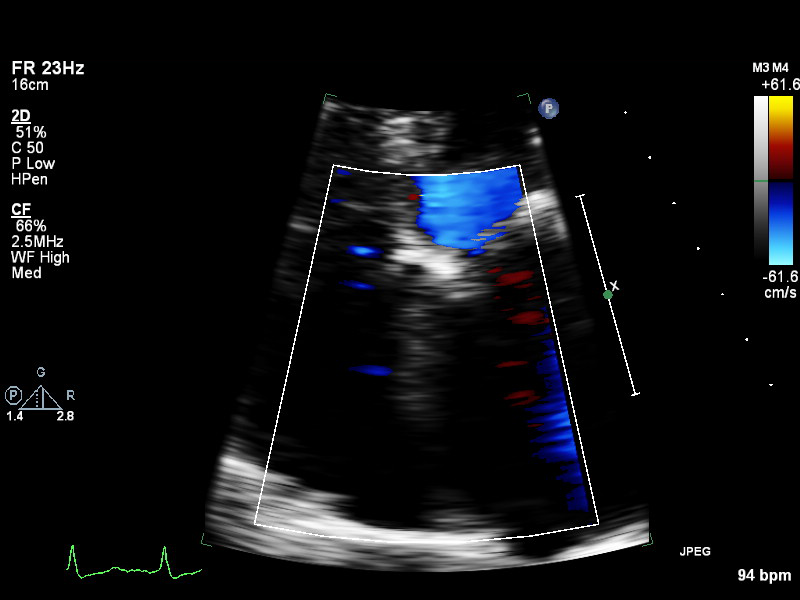

a4ch-ra a4ch-ra Apical 4-chamber focused on the right atrium, or colour Doppler on TV/RA

a4ch-rv a4ch-rv Apical 4-chamber focused on the right ventricle